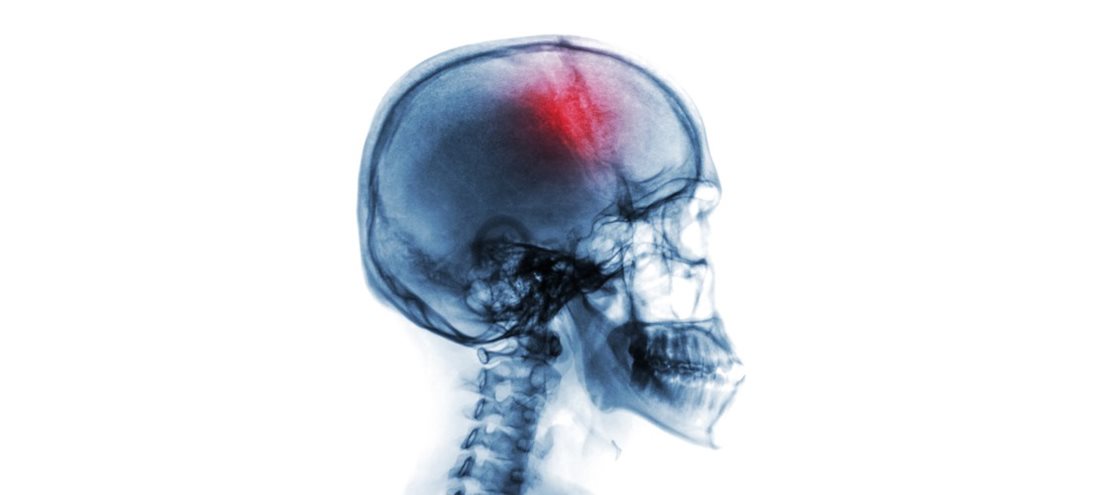

Afin d’assurer une pratique optimale des soins de l’accident vasculaire cérébral (AVC), une nouvelle formation visant l’amélioration de la collaboration des intervenants qui ont à prendre en charge rapidement cette pathologie chronodépendante est maintenant offerte.

Comme l’AVC est une pathologie chronodépendante, la rapidité d’action et la qualité de la prise en charge de l’équipe de soins est essentielle. C’est pourquoi cette formation s’adresse à tous les intervenants – infirmières, candidates à l’exercice de la profession infirmière (CEPI), infirmières auxiliaire, candidate à l’exercice de la profession d’infirmière auxiliaire (CEPIA), ergothérapeutes, physiothérapeutes, nutritionnistes, orthophonistes et aux autres professionnels multidisciplinaires – qui sont impliqués dans le continuum de soins et de services des usagers ayant subi un AVC.

La standardisation de l’organisation des soins et des services de ce continuum permettra de réduire la mortalité et la morbidité associées à l’AVC, d’améliorer la qualité de vie des personnes ayant subi un AVC et celle de leurs proches et d’améliorer la performance du système de santé.